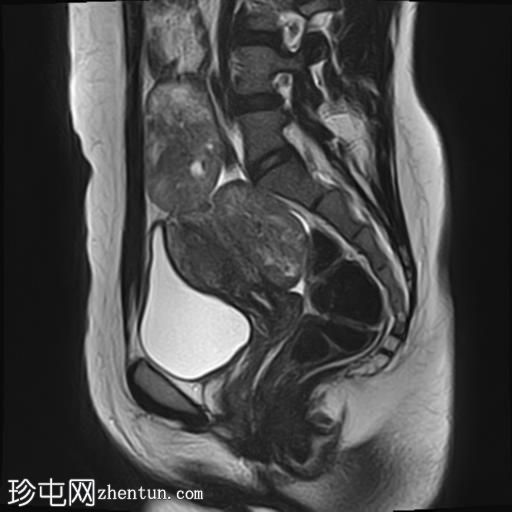

MRI

矢状位

T2加权像

其中一个位于子宫上方,T2加权像呈中等信号,中心区域呈高信号,增强T1脂肪抑制像未见强化。右侧卵巢增大,增厚的血管蒂扭曲,未见强化,轴位和矢状位T2加权像均显示清晰。

另一个位于子宫后窝,T2加权像呈中等信号,增强扫描显示明显强化。